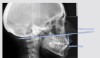

Fig 4. Lateral radiograph of patient with VME (anterior maxillary height: palatal plane-incisal edge = 29 mm to 31 mm).

Figure 4

Defining the proportions between the facial thirds of the face in frontal and lateral views will identify any alterations needed in the middle or inferior facial thirds. An increase in ratio of the middle third may indicate vertical maxillary excess (VME).6 Clinical assessment of the facial thirds is only approximative, and further radiographic imaging may be required (Figure 4). VME can be identified using a cephalometric analysis by localizing the distance between the incisal margins of the central incisors and the anterior nasal spine-posterior nasal spine (SPA-SPP) plane (palatal plane-incisal edge: 29 mm to 31 mm).7,11 However, the authors consider the cephalometric measurement—“palatal plane-incisal edge”—unreliable because the distance may vary depending on the amount of wear or in overeruption cases. Therefore, the authors suggest measuring the distance from the palatal plane to the cemento-enamel junction (CEJ) to eliminate any misleading data that might result from the presence of incisal wear, taking into consideration whether an altered CEJ position has resulted from compensatory overeruption.